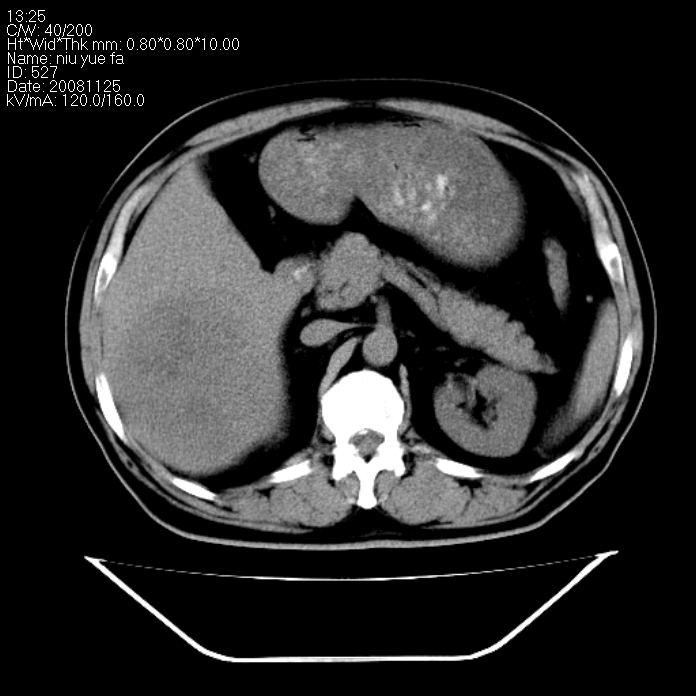

巨块型肝癌,坏死,出血;胆囊结石

1)考虑肝右叶巨块型肝癌并坏死、出血;建议行ct增强扫描检查进一步明确诊断。2)胆囊结石,胆囊炎。

考虑肝右叶巨块型肝癌并坏死、出血;建议行ct增强扫描。胆囊结石。

肝右叶巨块型肝癌并坏死、出血;胆囊结石,胆囊炎。